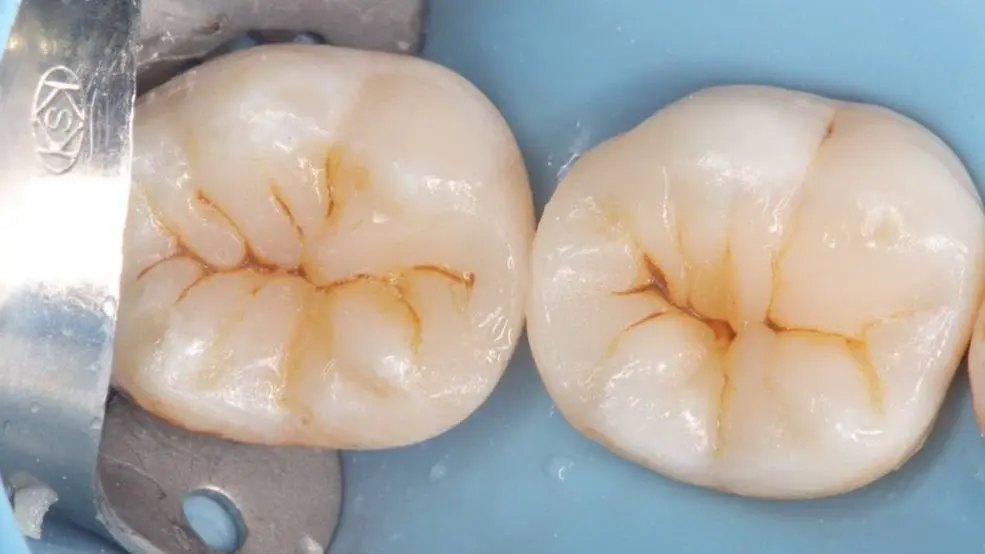

قبل

بعد